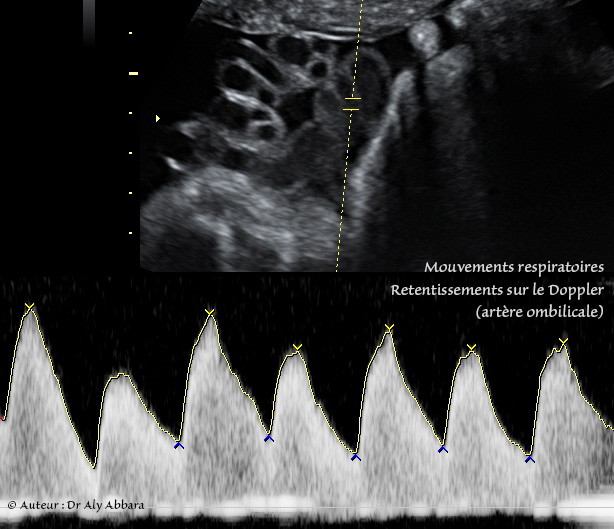

L'analyse spectrale du Doppler de la circulation artérielle fœtale montre que les mouvements respiratoires se manifeste par une irrégularité de la hauteur des pics systoliques et diastoliques en rapport avec les modifications de la pression dans la cage thoracique.